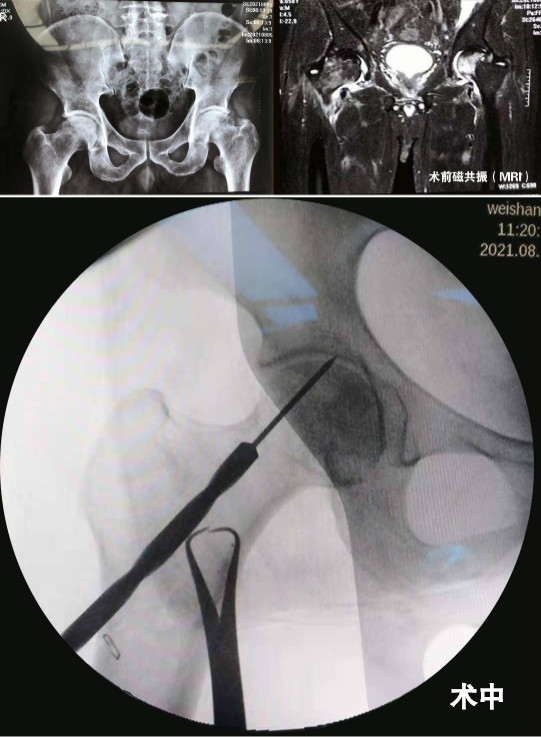

经赵琨主任详细询问病史,并结合影像学检查,确诊为股骨头坏死。赵琨主任向韩先生介绍了目前股骨头坏死早中期的多种保髋治疗方法,并就预后、并发症及相关术后康复锻炼作出详细解答,在与家人经过慎重考虑后,一致同意手术治疗。在赵琨主任主刀下,骨一科团队为其行“双侧股骨头坏死微创减压术”,术中精准减压,手术顺利完成,且创伤小。术后一天,在医生的指导下,韩先生就可以自行活动了。韩先生表示,骨一科的医护人员不仅技艺精湛,为人还很和善,住院期间有啥大事小情,都随叫随到,我们只能用一面锦旗表达内心感谢!

我们根据股骨头坏死的分期不同,根据患者病情“量体裁衣”制定个体化方案,除常规开展微创精准减压治疗股骨头坏死外,对于中末期股骨头坏死即髋关节发育不良导致的继发性股骨头坏死及骨关节炎行全髋关节置换术亦取得了良好的手术效果。